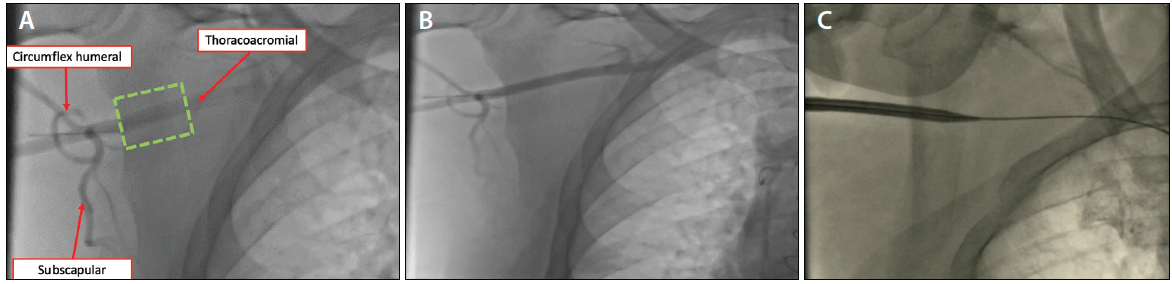

The axillary artery has been shown to be an acceptable alternative access site for large sheaths for both TAVR and MCS in patients with severe peripheral artery disease.34,35 The axillary artery originates from the subclavian artery as it passes out of the rib cage at the lateral margin of the first rib, where it becomes extra thoracic. The axillary artery is divided into three segments based on its relation to the pectoralis minor muscle. During angiography, those segments can be identified by the origin of the arterial branches: the superior thoracic artery emerges from the first segment, the thoracoacromial and lateral thoracic arteries from the second segment, and the subscapular artery from the third segment. The caliber of the axillary artery ranges from 6 to 7 mm, which makes it suitable to accommodate sheaths with an outer diameter of up to 18 F (Figure 6A).

The patient is prepared and draped in a supine position with the arm abducted at 90° away from the body. A 6-F sheath is placed in the ipsilateral radial artery or in either femoral artery. A 5-F Judkins right (JR) 4 guide catheter is advanced over a guidewire via the femoral artery and selectively engaged in the left subclavian artery or innominate artery. Angiographic assessment and identification of the axillary artery branches are important to precisely define the access point that is lateral to the thoracoacromial artery and medial to the circumflex humeral and subscapular arteries (ie, the “sweet spot”) (Figure 6A). Once the appropriate axillary artery site is identified, local anesthesia is administered 2 to 3 cm lateral to the sweet spot.

Figure 6. Angiographic assessment and identification of the axillary artery branches is important to precisely define the access point that is lateral to the thoracoacromial artery and medial to the circumflex humeral and subscapular arteries (ie, the “sweet spot”) (dotted green box) (A). A JR 4 or multipurpose catheter is used to engage the innominate artery to perform contrast angiography to identify the axillary artery anatomy (B). Introduction of the large sheath in the right axillary artery over the stiff wire (C).

There are three ways to target the sweet spot with the access needle. First, one JR 4 or multipurpose catheter is used to engage the left subclavian artery or the innominate artery to perform contrast angiography to identify the axillary artery anatomy and identify the sweet spot (Figure 6B). In cases when there is a contrast limit, wire-guided access is often used. In this technique, a 0.038-inch wire is advanced in the axillary artery and into the brachial artery. After one contrast injection, the sweet spot is identified, and the operator targets the wire over the sweet spot using live fluoroscopy. Similar to the guidewire technique, the operator can use a pigtail catheter to target the sweet spot. Alternatively, the axillary artery and landmark vessels can be identified with ultrasound precluding fluoroscopy. A micropuncture needle is then advanced under angiographic guidance at an angulation of ≤ 45° from the skin toward the access point that is lateral to the thoracoacromial artery (between the second and third segment of the axillary artery), immediately medial to the shoulder (Figure 6B). A 0.035-inch J-tip wire is then advanced into the subclavian artery and the micropuncture sheath is exchanged for a 6-F sheath. We dilate the tract with a 7- or 8-F sheath prior to introducing the Perclose ProGlide devices to prepare the access. Utilizing the “preclose” technique, two Perclose ProGlide suture-mediated closure devices are deployed at the 10 o’clock and 2 o’clock positions, respectively, and left uncinched. The arteriotomy is then sequentially dilated prior to introduction of the large sheath over a stiff 0.035-inch wire of choice (Figure 6C).